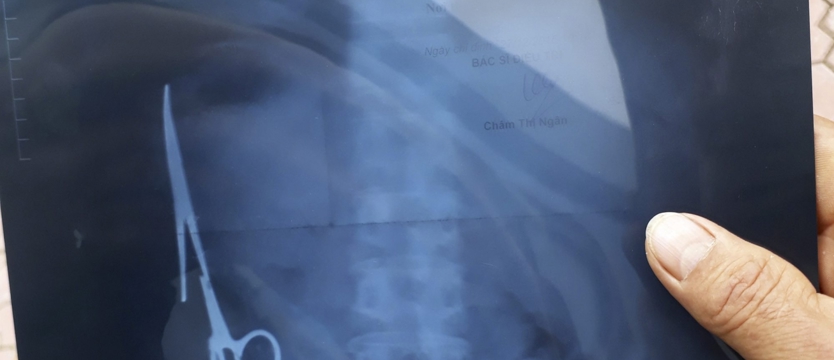

Z żołądka mężczyzny po 18 latach wyjęto nożyczki

Wietnamscy chirurdzy wyjęli z żołądka mężczyzny 15-centymetrowe nożyczki, które miał w brzuchu od czasu operacji przeprowadzonej 18 lat wcześniej. Pacjent przez lata funkcjonował bez problemów.

Mieszkający niedaleko Hanoi mężczyzna w 1998 roku po wypadku drogowym został poddany operacji chirurgicznej, w czasie której omyłkowo zaszyto mu w brzuchu nożyczki. Wykryto je dopiero podczas niedawnego badania ultrasonografem, zleconego ze względu na bóle brzucha, na jakie skarżył się pacjent.

Chirurdzy ze szpitala w Gang Thep Thai Nguyen, ok. 80 km od Hanoi, wyjęli nożyczki w czasie 3-godzinnej operacji. Jak zapewnił w rozmowie z AFP przedstawiciel szpitala, pacjent czuje się dobrze. Cytowany przez lokalne media rzecznik ministerstwa zdrowia powiedział, że mężczyzna przez prawie 20 lat "żył normalnie", mógł bez problemów jeść i pić. Obecnie wietnamskie władze poszukują lekarzy, którzy przeprowadzili niefortunny zabieg w 1998 r.